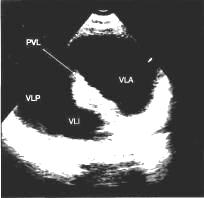

Эхокадіографія (УЗД) - сьогодні

найважливіший і інформативний метод дослідження, який дозволяє поставити точний

діагноз. Завдяки УЗД вперше в історії з'явилася пряма можливість побачити серце

дитини до пологів, а сучасні методи дозволяють діагностувати вроджену ваду

серця при вагітності усього в кілька тижнів. Насамперед помітні вади, при яких

будова серця різко порушена, тобто дуже важкі й складні для виправлення надалі.

Г,й)

У народженої дитини УЗД дозволяє

визначити наявність або відсутність структурних змін. Крім того, дає можливість

визначити тиск у порожнинах серця, різницю тиску між камерами, установити

величину й напрямок скидання крові, якщо він є, товщину стінок передсердь і

шлуночків. Й)

УЗД дає можливість спостерігати за

перебігом вади серця в динаміці - тобто бачити, що відбувається із серцем , як

воно реагує, у якому напрямку йдуть зміни - до поліпшення або, навпаки, до

погіршення. Іншими словами, воно може дати сигнал - чи треба активно

втручатися, щоб допомогти, і коли, щоб не було занадто пізно. І, якщо

врахувати, що метод цей - неінвазивний, абсолютно безпечний і може бути

повторений неодноразово й безболісно - то зрозуміло, що він став основою

сьогоднішньої діагностики. А, є,й)